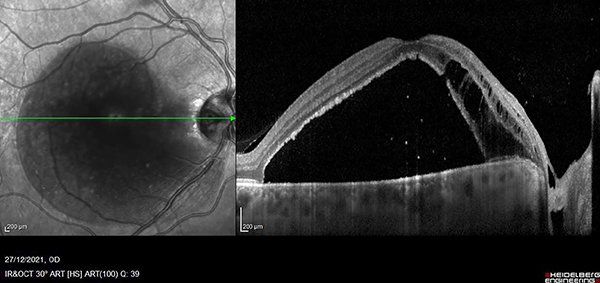

Al no presentar respuesta ante los tratamientos recibidos, reinterpretamos el cuadro clínico, observando detenidamente en el fondo de ojo derecho y en OCT una lesión compatible con foseta del disco óptico con filtración de líquido hacia el espacio subretinal (figs. 4 y 5).

Decidimos realizar tratamiento quirúrgico: vitrectomía por pars plana (VPP) con peeling de membrana limitante interna (PMLI) y aposición de flap sobre el pit, taponamiento con hexafluoruro de azufre y endofotocoagulación peripapilar (figs. 6 y 7).

Figura 4. Retinografía color de polo posterior derecho con alteración a nivel del margen temporal del disco óptico (flecha: pit de papila).

Figura 5. OCT de ojo derecho. En el nervio óptico, el espacio hiporreflectivo corresponde al pit de papila.

Figura 6. Imagen intraoperatoria que muestra la confección del flap de membrana limitante interna y su posicionamiento sobre el pit de papila. Acercamiento con lupa de contacto para mácula.

Figura 7. Imagen intraoperatoria con lupa de no contacto que muestra el peeling de la membrana limitante interna y el flap invertido sobre el pit de papila.